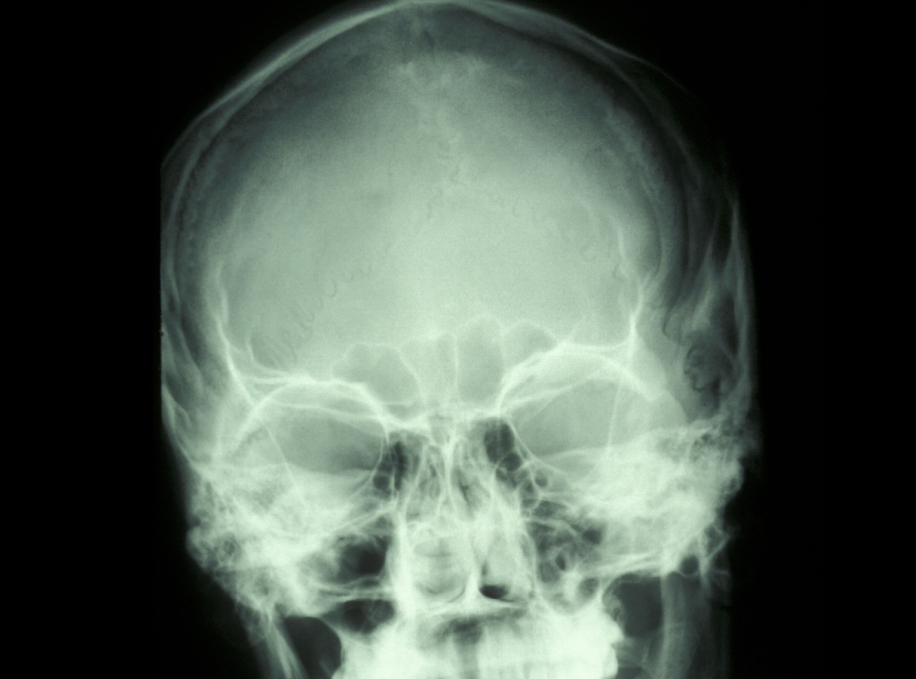

- displacement of the upper third molar into the maxillary antrum (one of the paranasal sinuses) or infratemporal fossa (cavity below the cheekbone), fortunately very rare (and scary!) (Figure 16);